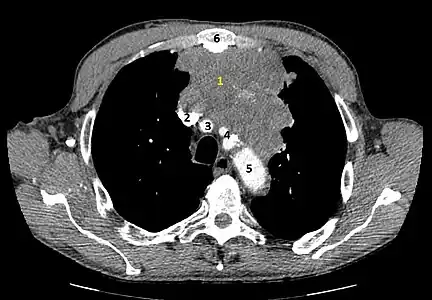

- Aspect scannographique

Présentation tomodensitométrique classique d'un thymome à un stade précoce (cercle rouge). À l'arrière, l'aorte, la veine cave supérieure et l'artère pulmonaire sont visibles en coupe.

Scanner injecté, en fenêtre médiastinale, montrant un carcinome thymique envahissant les structures médiastinales :

1 : tumeur hétérogène, aux contours irréguliers, présentant des plages hémorragiques ;

2 : veine cave supérieure ;

3 : tronc artériel brachiocéphalique ;

4 : artères sous-clavière gauche et carotide commune gauche ;

5 : crosse de l'aorte ;

6 : sternum.- Scanner en fenêtre parenchymateuse, montrant un carcinome thymique envahissant les poumons (avec des lésions d'emphysème) au contact des deux poumons (1 : poumon droit ; 2 : poumon gauche) ;

flèches noires : zones suspectes d'envahissement.